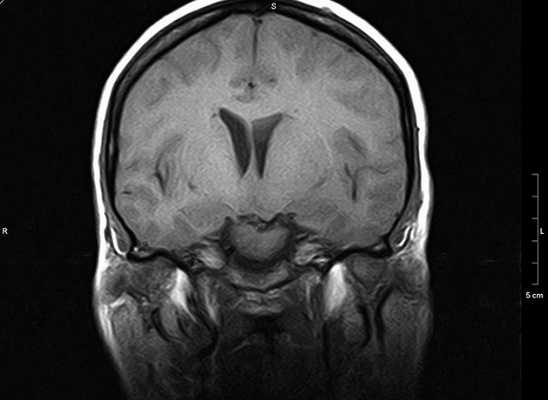

МРТ головного мозга. Корональная Т1-зависимая МРТ. Липома мосто-мозжечкового угла.

При МРТ в СПб мы не видим сложности в диагностике липом ни в высоких полях, ни в низких открытых МРТ, однако, выявление при МРТ головного мозга такой ее локализации как мосто-мозжечковый угол требуют внимания ввиду того, что здесь встречаются другие сходные образования (эпидермоиды, опухоли). Об МРТ головного мозга при других кистах можно читать в специальной статье.